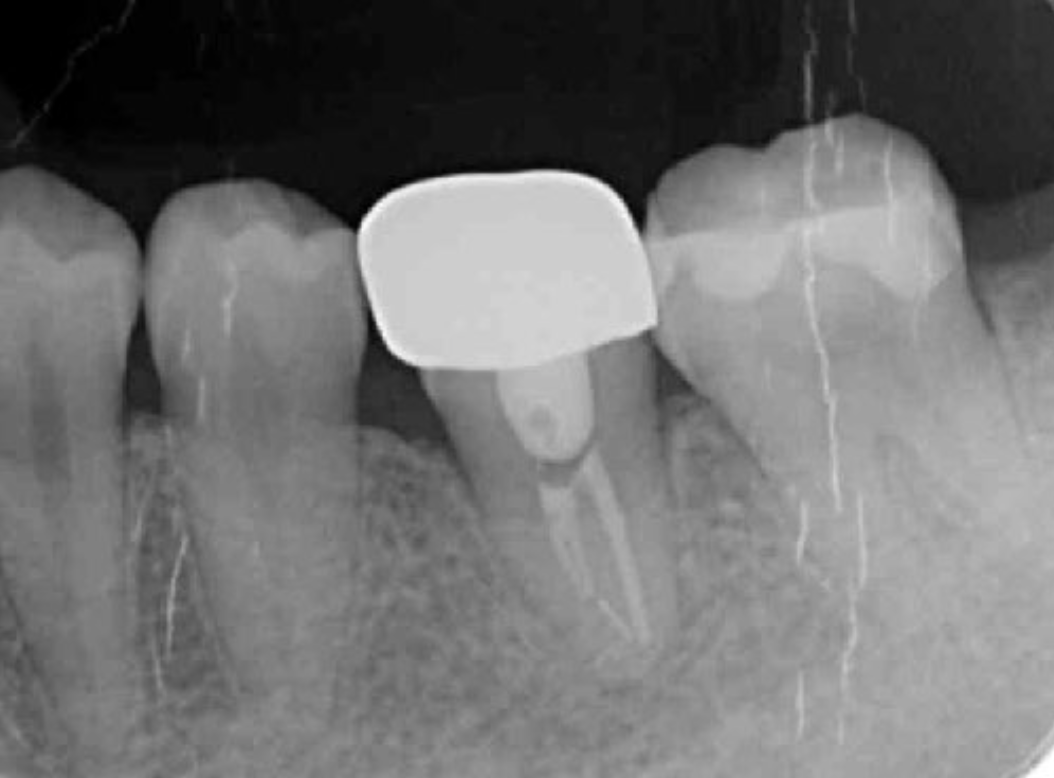

Endodontic treatment was initiated at 14 days after transplantation (8, 17). Root canal treatment for #48 was performed using Ni-Ti files (Pro Taper Next, Dentsply Sirona, Tokyo, Japan) to accommodate the complex morphology of the root canal and for minimal removal of the tooth structure during formation of the access cavity. Root canals were medicated with calcium hydroxide paste and then filled with gutta percha. The splint was also removed four weeks after the operation and a resin core was used as an abutment construction. In an attempt to appropriately modify contact and the crown morphology, a crown prosthesis was made with a full metal crown, with occlusal contact confirmed with use of a temporary crown and easy to visualize markings on occlusal paper. The full metal crown was cemented six months later (Figure 7).

Bone regeneration was confirmed before and after grafting, after root filling, and after placement of the prosthesis, based on X-ray imaging results (Figure 8). There was no pathologic mobility or pain during mastication, and the tooth showed good function. The patient was very satisfied with the treatment results (Figure 9).

Figure 7.Inter-oral photo obtained after treatment. Full metal crowns were inserted for #46, #47. Pathological mobility and bleeding on probing were not seen, and the transplanted tooth showed good function.

Figure 8.Cone beam CT image obtained after transplantation. Bone regeneration around the grafted tooth was confirmed.